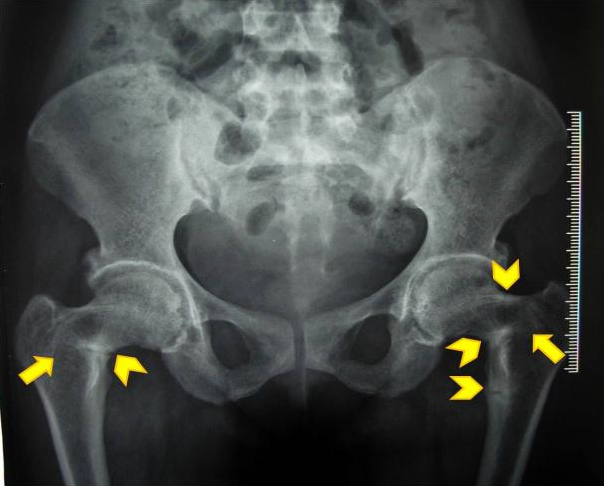

Các triệu chứng của nhuyễn xương ít nhiều có liên quan đến các nguyên nhân như: đau cơ và khớp (đặc biệt là cột sống, xương chậu, xương chân), yếu cơ, đi lại khó khăn, dáng đi lạch bạch, hạ canxi máu (khi thăm khám nhận thấy biểu hiện Chovstek - một dấu hiệu lâm sàng do thần kinh bị kích thích), chèn ép đốt sống và thấp còi, xương chậu dẹt, yếu, xương mềm và dễ gãy, hoặc bị cong. Ở người lớn, nhuyễn xương thường tiến triển âm thầm, gây đau nhức ở vùng cột sống (thường là cột sống thắt lưng) và bắp đùi trước khi lan sang cánh tay và xương sườn [2]. Cơn đau thường đối xứng, không lộ rõ và gắn liền với cảm giác nhạy đau ở các xương liên quan, yếu gốc chi (đầu gần cơ), khó leo trèo, khó khăn khi lên cầu thang và khó đứng dậy khi ngồi xổm. Hình 2 là hình ảnh gãy giả xương đùi hai bên (mũi tên không thân màu vàng), hay còn gọi là vùng Looser (Losser’s zone). Đây là hình ảnh đường giảm xuyên thấu tại vùng xương nằm ngay ngoài các động mạch lớn. Một số chuyên gia cho rằng, hình ảnh này tạo nên bởi dòng máu chảy qua động mạch, do đó chỉ nhỏ khoảng vài mm chiều rộng và vài cm chiều dài, thường thấy ở xương đòn, xương chậu và cổ xương đùi.

Hình 2. Hình ảnh gãy giả xương đùi hai bên (mũi tên không thân màu vàng) [3].